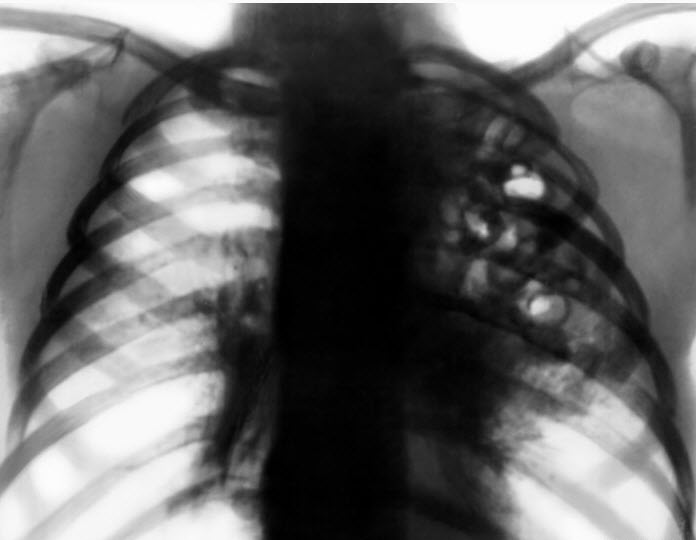

Наиболее часто клинически легионеллёз диагностируют как тяжёлые пневмонии (собственно «болезнь легионеров»). В первые дни заболевания у части больных можно наблюдать продромальные явления в виде головной боли, слабости, снижения аппетита, возможно развитие диареи. При остром начале болезни быстро повышается температура до 39-40 °С, нарастают признаки тяжёлой интоксикации. Больные жалуются на озноб, головную боль, боли в мышцах и суставах, выраженную потливость. Развиваются общая слабость, адинамия. Появляются признаки токсического поражения ЦНС: эмоциональная лабильность, заторможенность, обмороки, галлюцинации, потеря сознания и бред. Иногда наблюдают атаксию, дизартрию, нистагм, паралич глазодвигательных мышц. К середине недели возникает кашель, сначала сухой, затем со скудной слизисто-гнойной, а у части больных с кровянистой мокротой. Развиваются одышка, сильные боли в груди, особенно при сопутствующем фибринозном плеврите. В лёгких выявляют притупление перкуторного звука, участки ослабленного дыхания, большое количество сухих и влажных мелкопузырчатых хрипов. Почти у половины больных выслушивают шум трения плевры. На рентгенограмме определяют очаговые инфильтраты разнообразной локализации; впоследствии они сливаются и образуют обширные очаги затемнения по типу долевой, а довольно часто односторонней субтотальной и даже тотальной пневмонии.